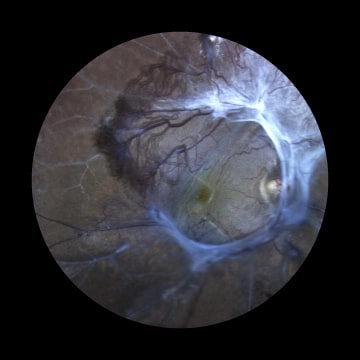

Retinal diseases may be inherited or acquired disorders. They can affect the young and old. Eg. Diabetic Retinopathy, Retinal Detachment, Retinal Vascular Occlusions, Age Related Macular Degeneration, Retinitis Pigmentosa, Retinopathy Of Prematurity and Retinoblastoma ( Cancer of the retina) etc.